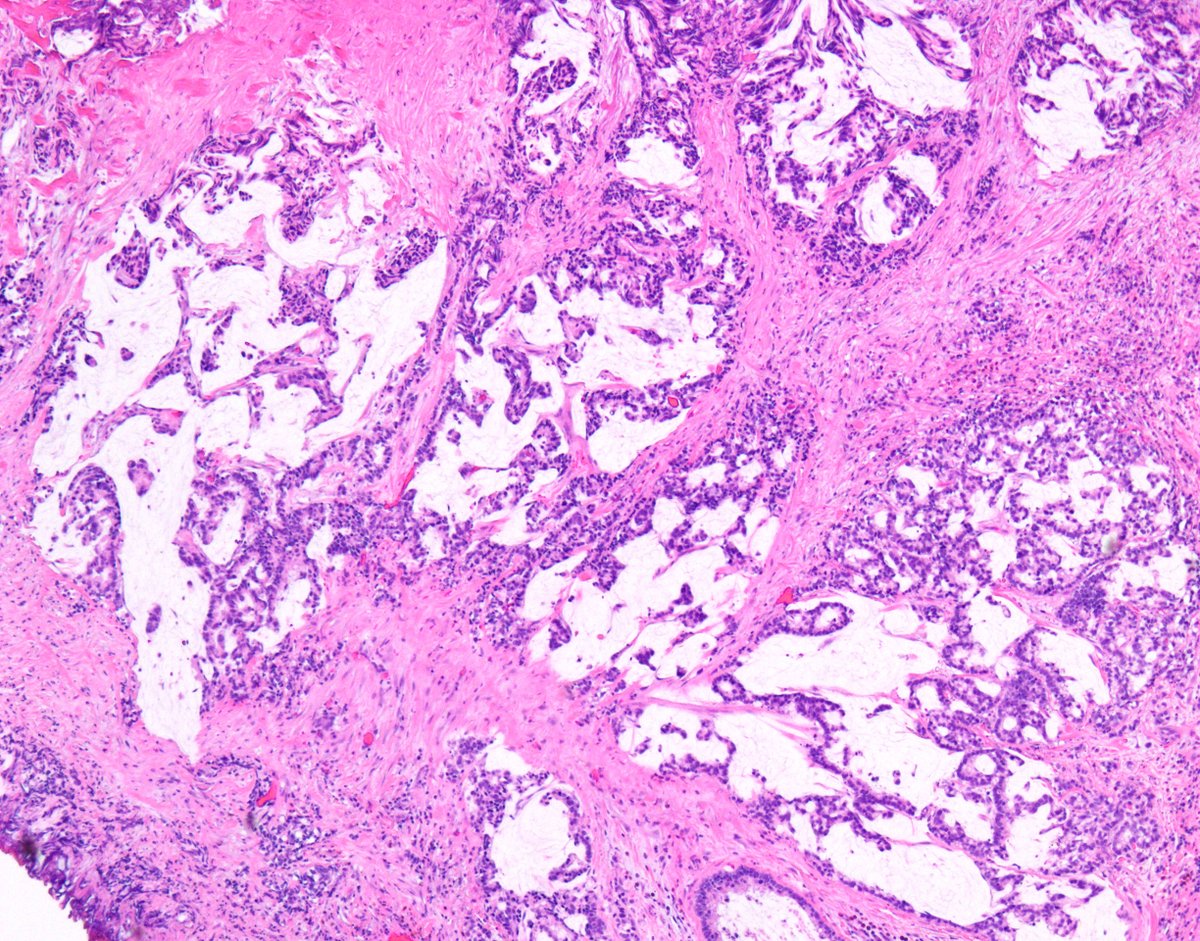

@GladellPaner

Tubulocystic renal tumor with a twist. 👀 What’s your top diagnosis #GUPath tweeps? #OnePicDx Answer in comment. 👇🏻👇🏻👇🏻

3

28

118